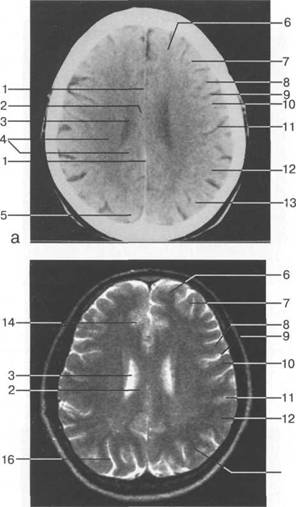

Задняя череп 13513u2010n 85;ая ямка представляет собой часть основания череп 13513u2010n 72;, ограниченную централь

Следует отметить, что в настоящее время оптимальным методом исследования структур задней череп 13513u2010n 85;ой ямки является МРТ, которая, в отличие от КТ, лишена артефактов от кост

Мозжечок заполняет практически весь объем задней череп 13513u2010n 85;ой ямки. Его поперечный раз

Следует остановиться на анатомии подпаутинных пространств задней череп 13513u2010n 85;ой ямки IV 20 мм. Между основанием череп 13513u2010n 72; и нижней поверхностью мозга от большого затылочного отверстия вдоль ската и спинки турецкого седла простирается задняя базальная цистерна. В зави IV